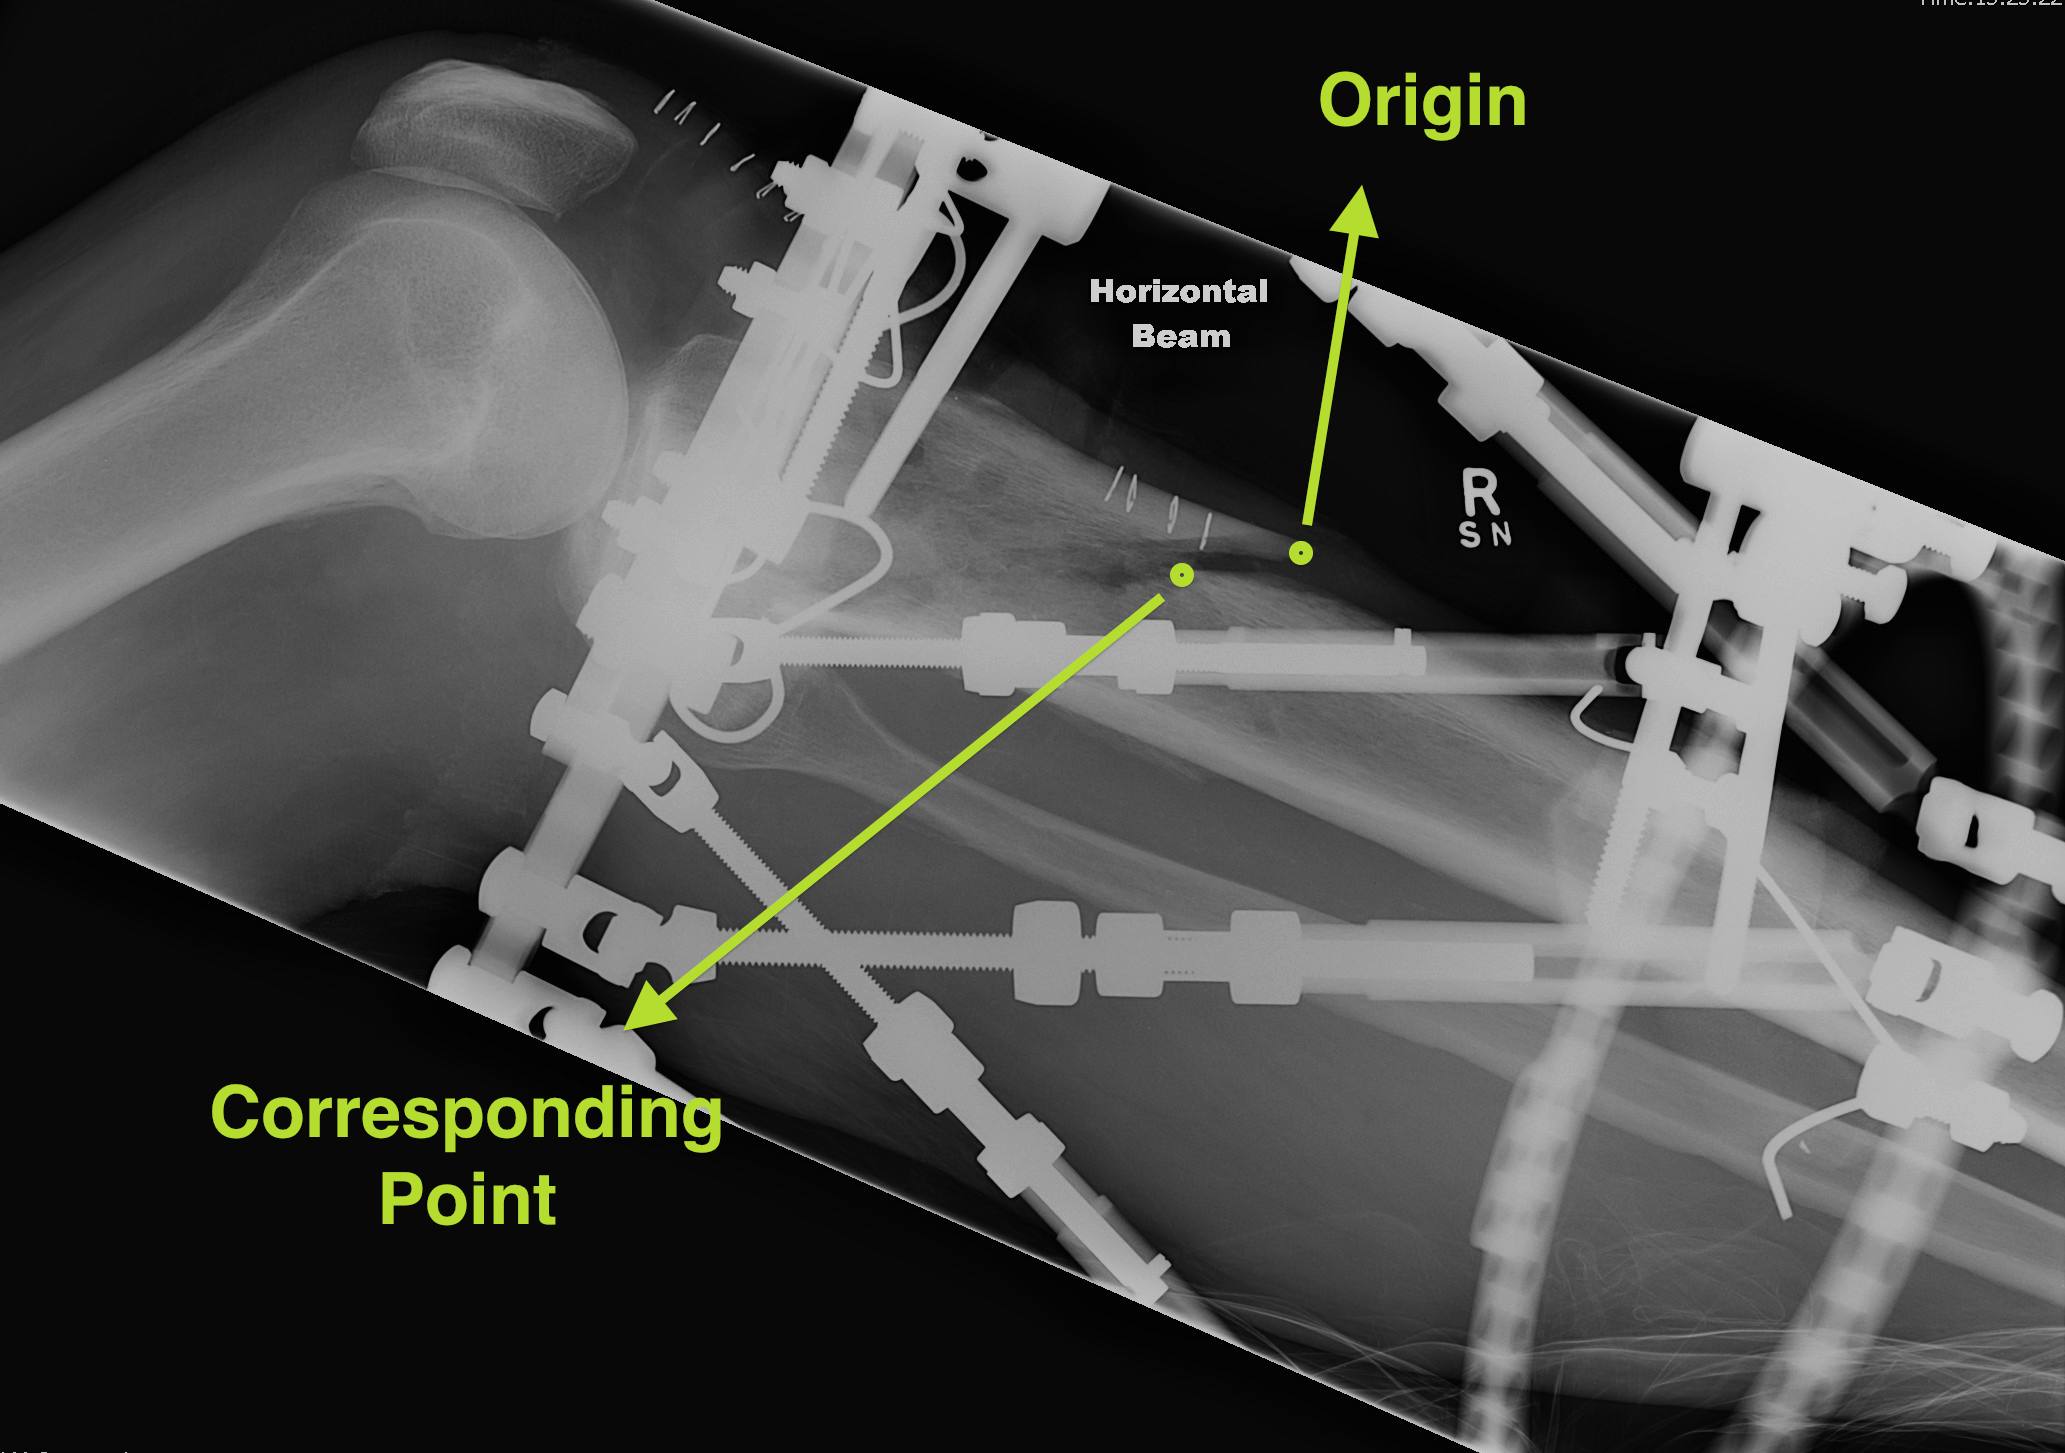

Set Origin / Corresponding Point on AP and Lateral

Origin

- reference fragment

Corresponding point

- on moving fragment